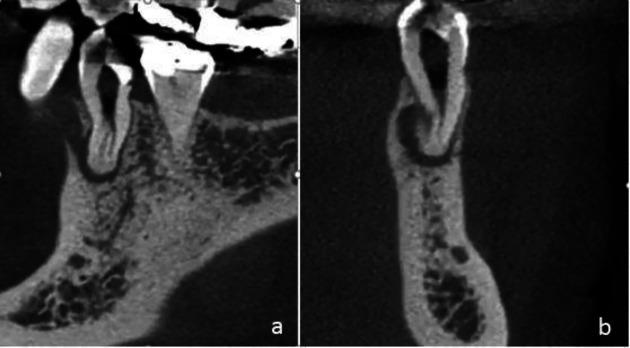

Our article aimed to present a curious case of a mandibular premolar with a C-shaped root canal and to review the available literature on this anatomical variation. Mandibular premolar teeth account for the greatest endodontic challenges in the course of treatment on account of the morphological variations in their root canal systems, including extra root(s)/canal(s) or a C-shaped configuration. A 20-year-old female patient was referred to the Department of Endodontics of Mashhad Faculty of Dentistry, suffering from abscess, and pain while chewing. On examination the culprit was found to be the left mandibular first premolar. Following special tests and periapical radiography, we found an amalgam restoration proximate to the non-vital pulp chamber, as well as an unusually complex root canal anatomy with periapical radiolucency. A non-surgical root canal treatment with the aid of a dental operating microscope was considered as the treatment plan. Clinicians should always anticipate the presence of a C-shaped configuration in mandibular premolars, and make use of all the available tools to locate and treat such cases. A substantial knowledge of root canal anatomy would be prudent to ensure a successful outcome ensuing surgical and non-surgical root canal treatments.

我们的文章旨在呈现一例具有C形根管的下颌前磨牙的罕见病例,并回顾有关这种解剖变异的现有文献。由于下颌前磨牙根管系统存在形态变异,包括额外的根/根管或C形结构,因此在治疗过程中,它们是牙髓治疗面临的最大挑战。一名20岁女性患者因脓肿和咀嚼时疼痛被转诊至马什哈德牙科学院牙髓病科。检查发现罪魁祸首是左下颌第一前磨牙。经过特殊检查和根尖周X线片检查,我们发现靠近无活力牙髓腔处有银汞合金修复体,以及异常复杂的根管解剖结构和根尖周透射区。治疗方案考虑在牙科手术显微镜辅助下进行非手术根管治疗。临床医生应始终预期下颌前磨牙存在C形结构,并利用所有可用工具来定位和治疗此类病例。为确保手术和非手术根管治疗取得成功结果,对根管解剖有充分了解是明智的。